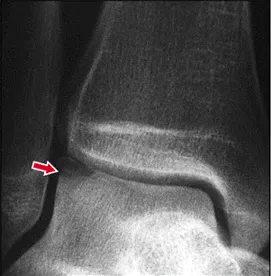

Ankle arthroscopy involves the surgical evaluation and treatment of the ankle for conditions such as chronic ankle pain, ankle trauma, cartilage defects, ligament repairs, and a variety of other conditions.

Arthroscopy involves the use of a fiberoptic camera and small surgical instruments simultaneously. The instruments are used through small incisions compared to traditional open surgery. Dr. Tu is certified in arthroscopic foot and ankle surgery.

Above is a cartilage defect that was identified then repaired using arthroscopy

• You may need ankle arthroscopy if you have debris in your ankle from torn cartilage or from a bone chip. Also, if there is ligament damage from a severely sprained ankle, a foot and ankle surgeon may choose to do an arthroscopy to evaluate the extent of damage and possibly to repair it.